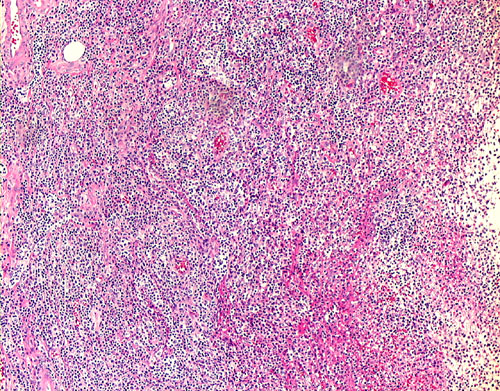

9. Pulmonary Sarcoidosis

9-4.jpg (121193 bytes)9-10.jpg (126243 bytes)9-20.jpg (133850 bytes)9-40.jpg (91520 bytes)